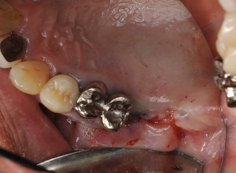

人工骨に再生医療で使われるCGFを混ぜています。採血管をプラスチックにすることによりCGFが液体状になり、人工骨と混ぜやすくなります。

サイナスリフトとインプラント同時埋入しています。この場合だいたい9か月ほど

インプラントが骨に結合するまで待ちます